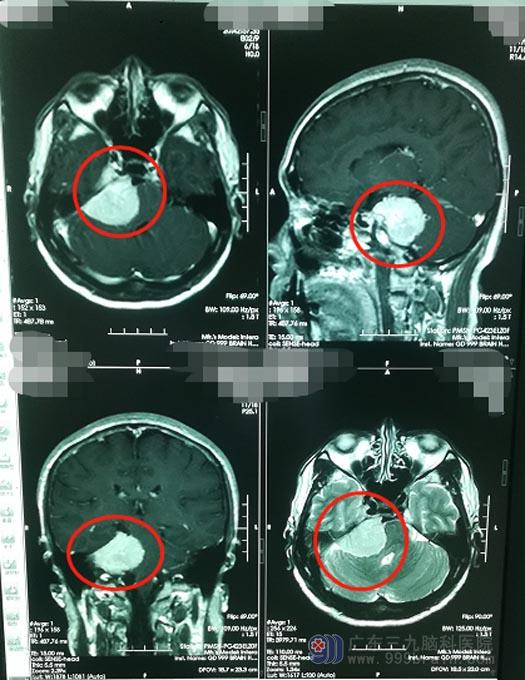

在家人的多方打听和不断鼓励下,邓大哥来到了广东三九脑科医院神经外五科。接诊的医院副院长、神经外五科主任鲁明仔细地查看了患者的影像资料,初步考虑是“右侧岩斜区跨中后颅窝占位,良性的脑膜瘤可能性比较大”。

脑膜瘤是一种常见的颅内肿瘤,大多为良性,可以生长在颅脑多个部位,其中以生长在岩斜区的脑膜瘤最为可怕。岩斜区是指位于颞骨岩部背面与枕骨斜坡部的岩斜裂汇合处,从岩骨尖至颈动脉孔,构成中后颅窝的一片区域。发生在此区域的脑膜瘤生长方式复杂多变,常常沿着颅底朝多个方向生长,可累及12对脑神经中的11对,毗邻脑干、椎基底动脉和颈内动脉等重要神经血管,堪称“恶性区域”。颅底岩斜区脑膜瘤的治疗颇为棘手,它代表了颅底手术中最难的一类,因为瘤体位置特殊显露困难,故手术风险大,死亡率和致残率高,因此,是神经外科领域中最具挑战性的手术,对手术医生的病变解剖及显微技术的要求非常高。

▲手术前